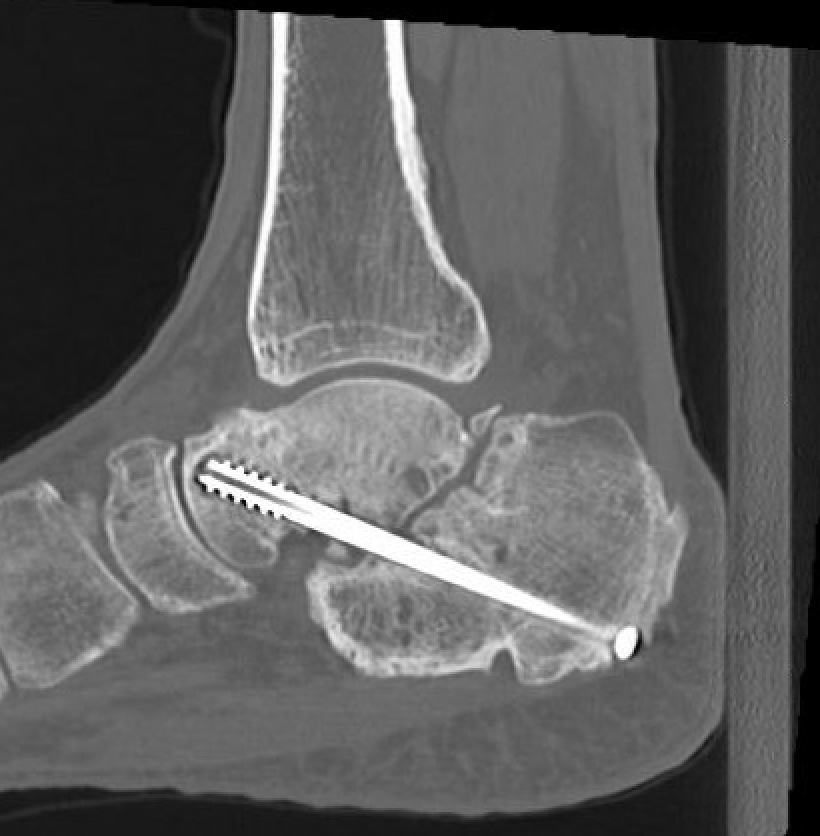

CT

Subluxation of TNJ with advanced STJ OA

TNJ OA with posterior / medial / anterior facet OA of the subtalar joint

Fixation

- 6.5 mm/ 8.0 mm cannulated screw

- inferior calcaneum into body and neck of talus / talus to calcaneum

- TJN screws

- CCJ screws +/- plate

- STJ screws